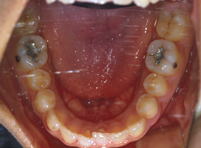

小さい頃に、大きなむし歯で左下の6歳臼歯を失ってしまい、ブリッジが入っていた方です。

(写真は、矯正治療前→矯正治療中→矯正治療後です。)

ブリッジを切断して、歯のない部分のすき間を矯正治療で閉じました。

(すき間が閉じているでしょう。歯は動くんです!)

左下の一番奥歯は、親知らずです。

矯正治療前は、ほんの少ししか見えていなかったのですが、治療後にはきれいにでてきて、きちんと並んでいます。